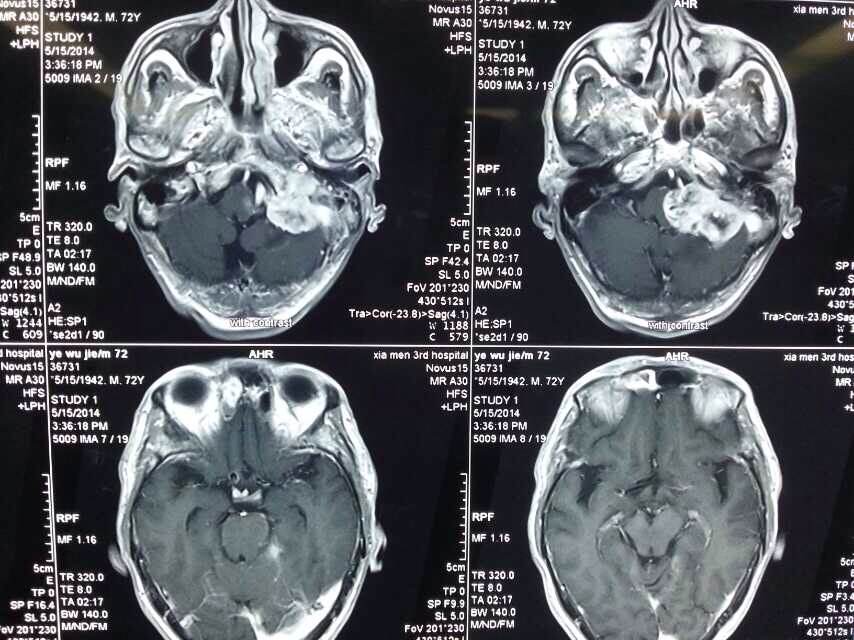

2014520是个特别的日子,第三医院手术室灯火通明,神经外科调集所有的技术团队手术一台接一台,有脑动脉瘤破裂的,有脑外伤出血的,忙碌不停。